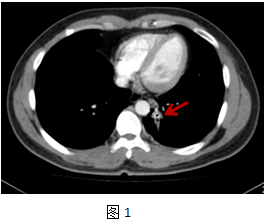

患者劉**,男,34歲,以“咳嗽咳痰2年余”為主訴入院。該患者近2年反復(fù)刺激性咳嗽,少量白粘痰,在當?shù)蒯t(yī)院反復(fù)抗感染治療無效。入院前胸部CT片顯示:左肺下葉后基底段結(jié)節(jié)性質(zhì)待定。肺病科徐順貴副主任醫(yī)師和胸外科陳陽天主任醫(yī)師仔細閱讀患者外院胸部CT片后發(fā)現(xiàn)左肺后基底段支氣管處有一圓柱型高密度影,考慮支氣管異物可能(圖1,2),詳細追問病史,患者9歲時嬉鬧時誤吸一玩具子彈,當時咳嗽較劇,后癥狀緩解。近2年患者間斷有咳嗽、咳痰,癥狀逐漸加重。